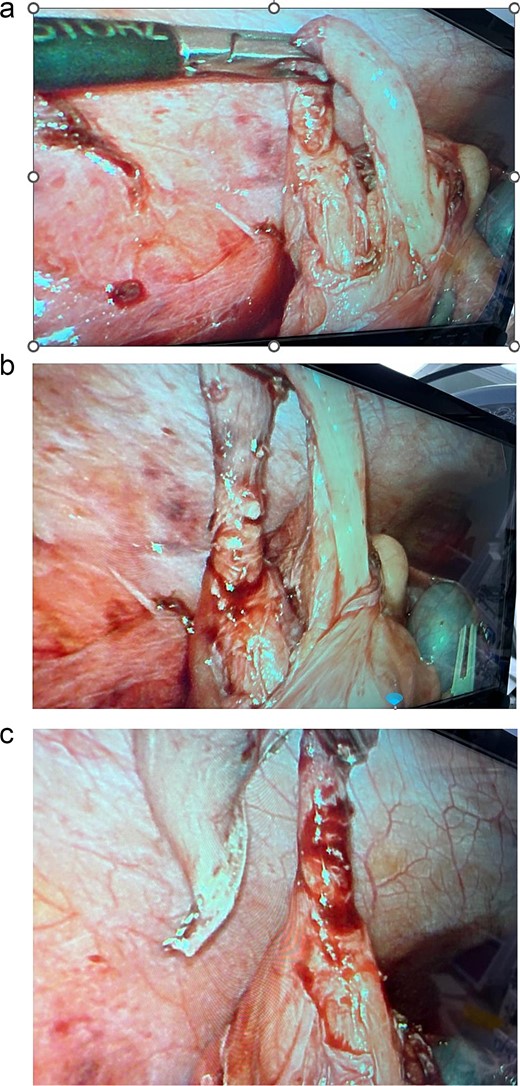

We are presenting a 19-year-old, single female patient, medically and surgically free, who presented to Emergency Department with a history of persistent right lower quadrant (RLQ) abdominal pain for 2 days, not improving and increasing in severity, no fever, and no previous similar attacks. On exam, she was stable, no tachycardia, no documented fever, and vital signs upon presentation: blood pressure 116/52 mmHg, heart rate 66 beats per minute, respiratory rate 20 frequency/min, saturating well 100% on room air. The abdomen exam was positive for RLQ tenderness, no rebound, negative Rovsing’s sign, no peritoneal signs. Labs were remarkable for white blood cells: 11.2 × 109/L and neutrophil shift: 8.92 × 109/L, other labs were within normal ranges; pregnancy and urinalysis were negative. Alvarado score was 7. Abdomen computed tomography (CT) scan done (Fig. 1) showed a dilated appendix up to 1 cm with mural edema and hyperenhancement surrounded by mild fat stranding, subcentimeter reactive lymph nodes, minimal free fluid, and thickened adjacent peritoneal reflection. There is no adjacent drainable collection. The unprepared small and large bowel loops are unremarkable. Impression was acute, uncomplicated appendicitis. Patient admitted, prepared for surgery, and laparoscopic appendectomy was planned on the same day of the admission. Intra-operatively, the cecum was identified, which was in the subhepatic area; we followed the taeniae coli; and the appendix was identified in the retrocecal area, and it had two bases, both of which were forming a horseshoe appearance, which is an anomaly of the appendix (Fig. 2). We dissected it off completely till the cecum. Decision made for stapling both bases with an endo-GIA 45 purple. Both bases were stapled. Clean bases were identified, and staple lines were clean, no bleeding, and it was completely healthy. Hemostasis was secured. The patient tolerated the procedure well. The patient was assessed the following day and was doing fine, tolerating orally, passing flatus, with an unremarkable abdominal exam. She was discharged the next day in stable condition. The patient was seen after 2 weeks from the discharge in the clinic and was doing well; clips were removed, and pathology confirmed the diagnosis of acute appendicitis with periappendicitis with a shape anomaly of the horseshoe appendix. Patient planned for colonoscopy in the outpatient department. Interval colonoscopy done that was unremarkable. Patient discharged from the clinic.

Intra-operative findings of the appendix with two bases connected to the cecum and forming a horseshoe appearance, which is an anomaly of the appendix.